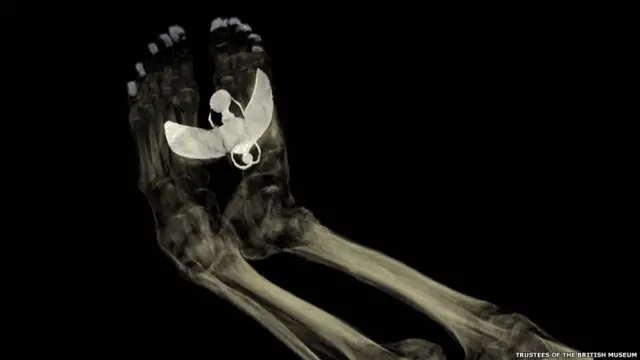

Новая экспозиция в Британском музее с помощью самых передовых технологий дает зрителю шанс заглянуть в прошлое и прикоснуться к жизни древних египтян.